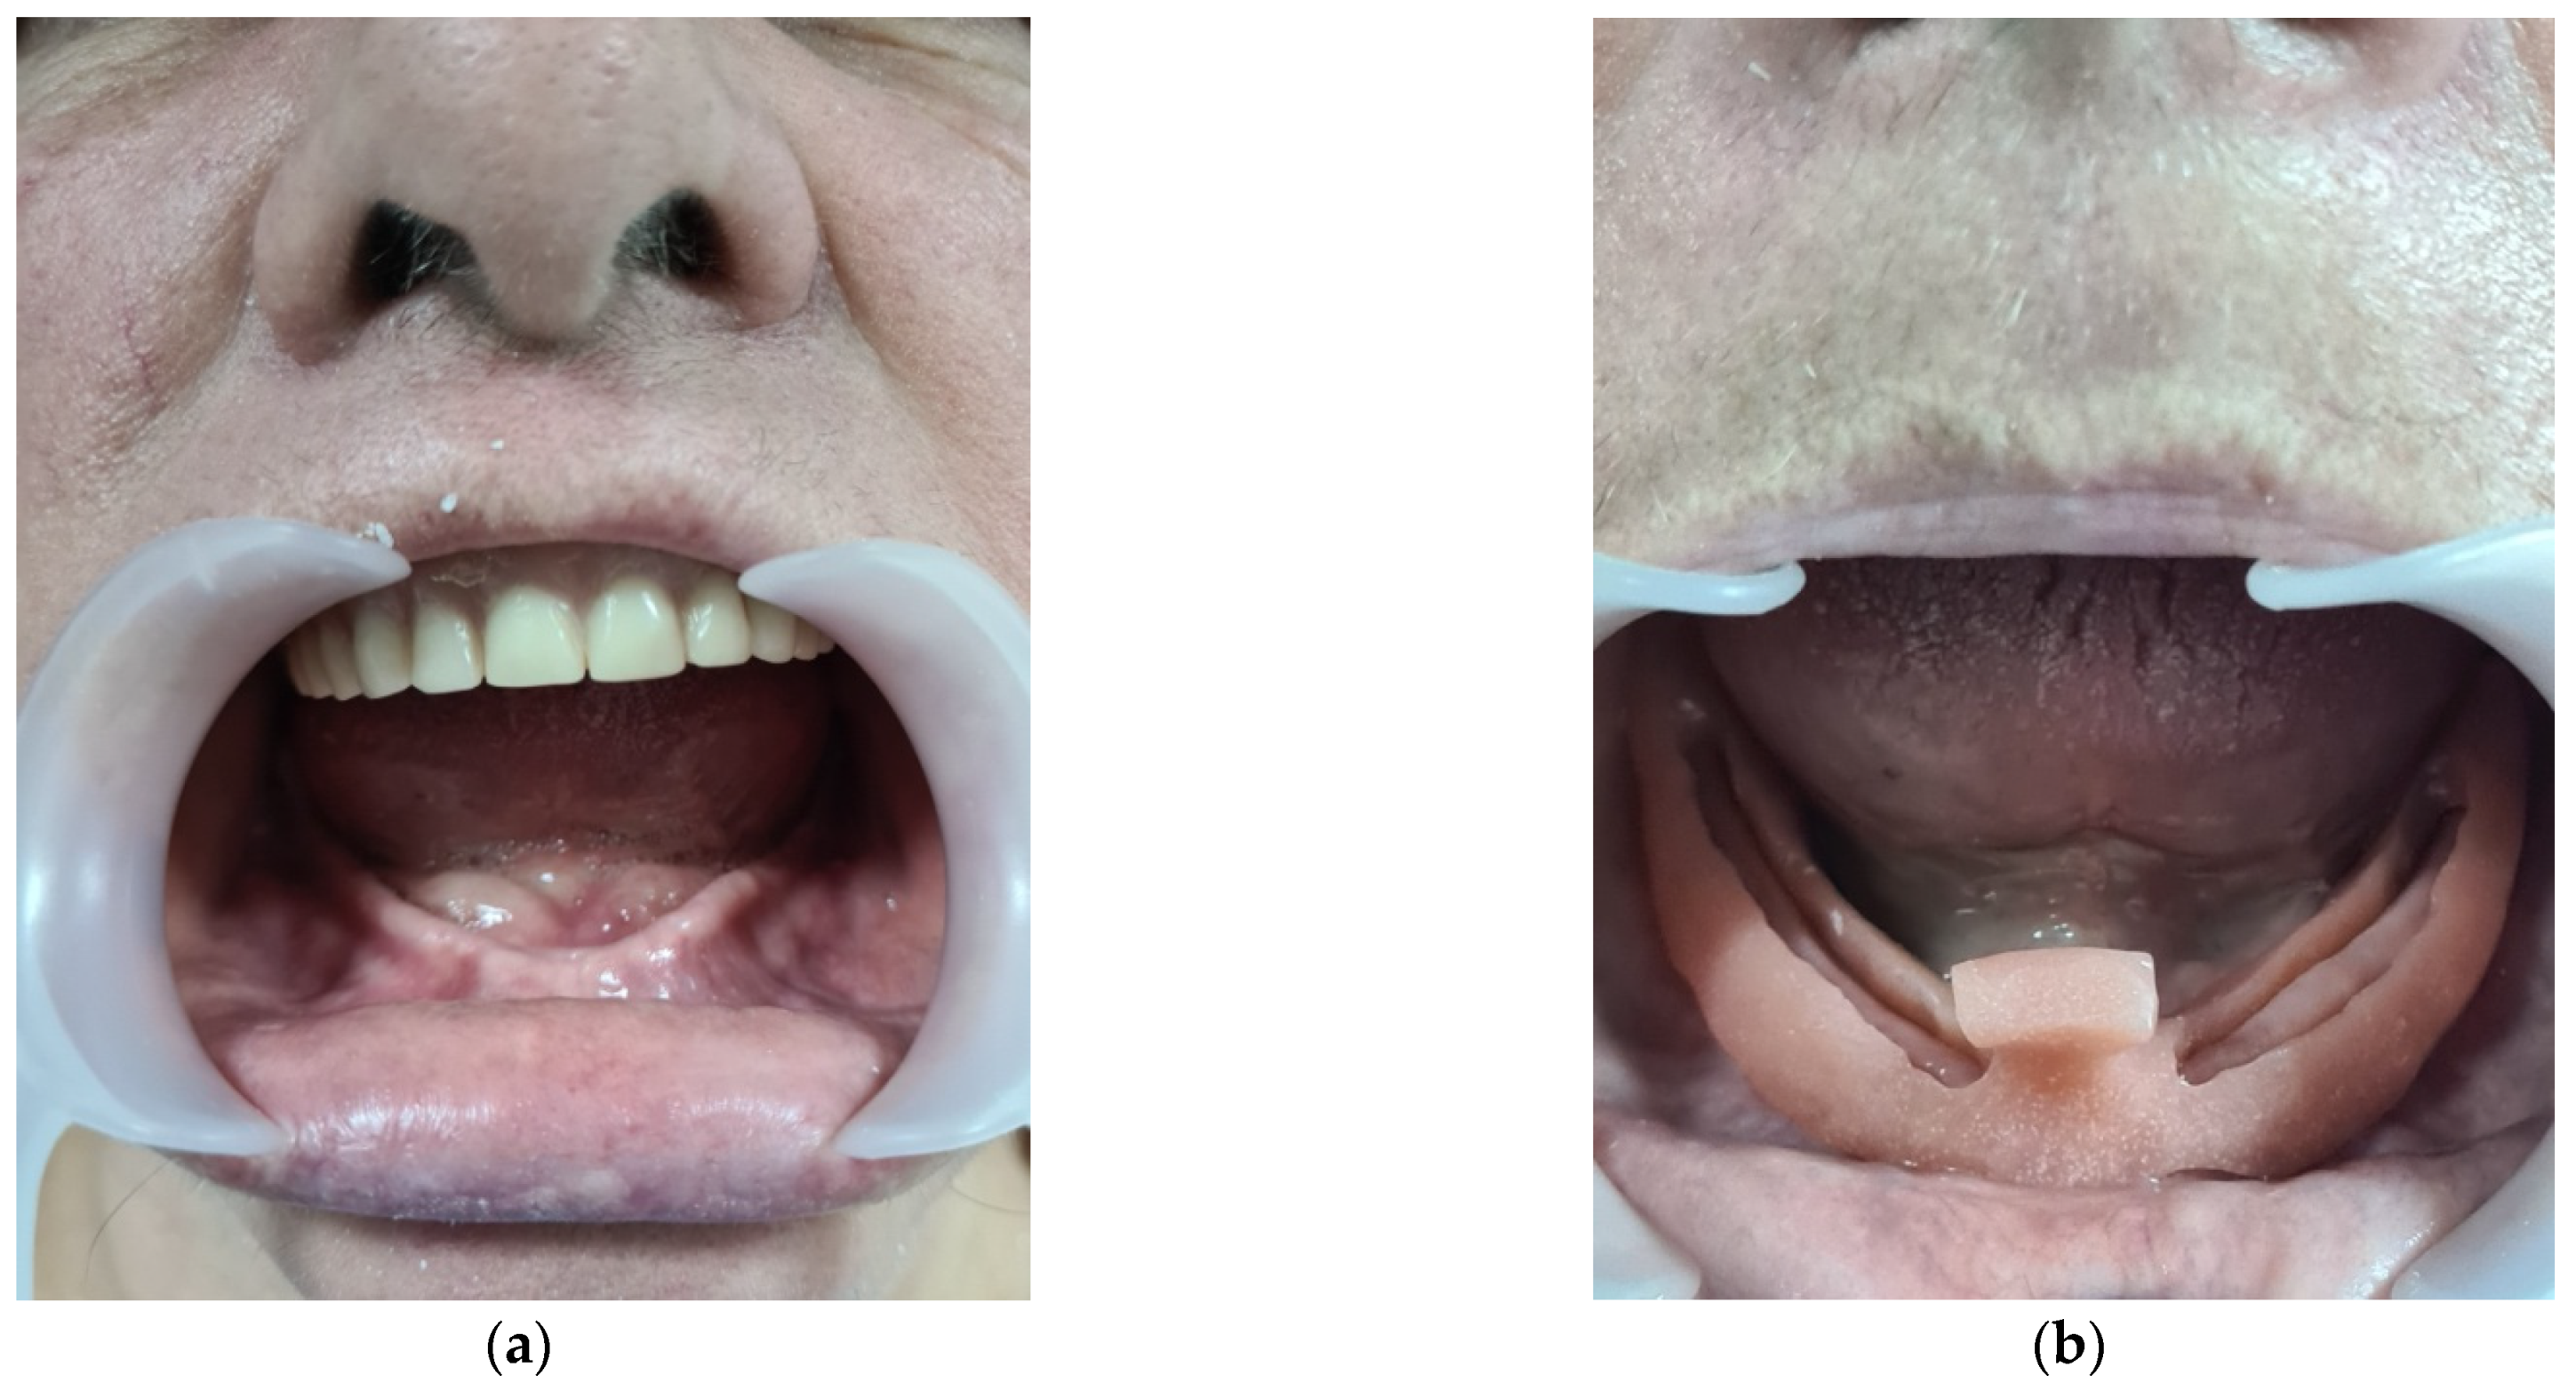

3.2. CASE REPORT 2